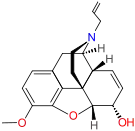

- Alletorphine (N-allyl-noretorphine)

Alletorphine Alletorphine |